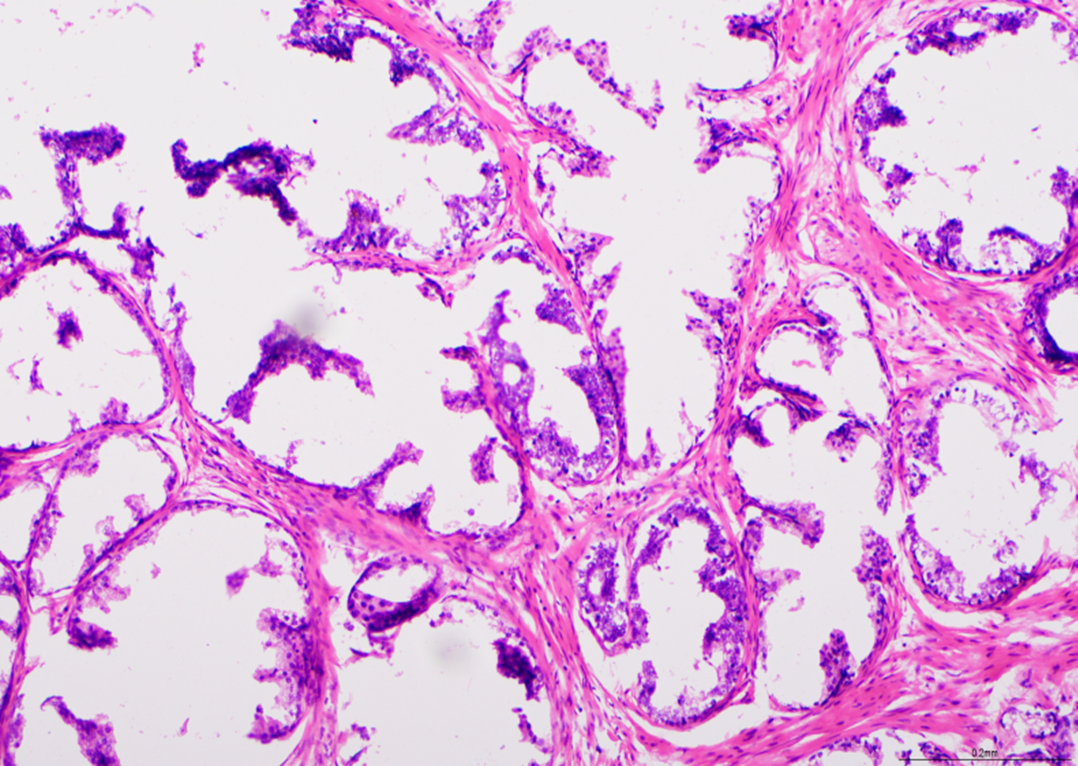

Glail-fibre - Neuropatologiskema

Set ved x20 er dette et eksempel på en teknik til demonstration af glailfibre. Farvningen set her er suboptimal med svage fibre. Dette scorede 7/10.